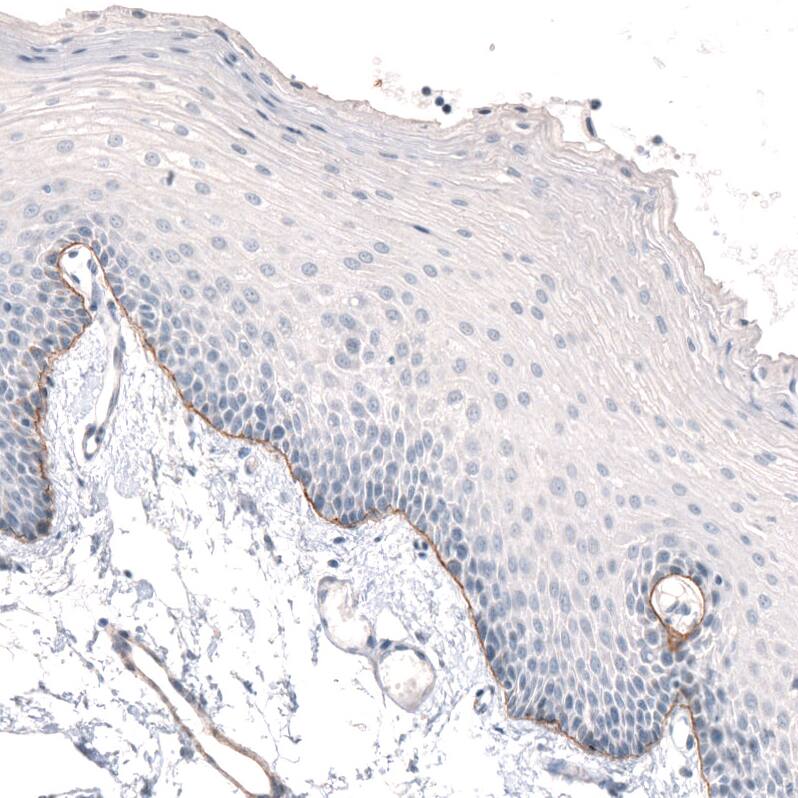

Staining of human oral mucosa shows moderate positivity in basement membrane of squamous epithelial cells.